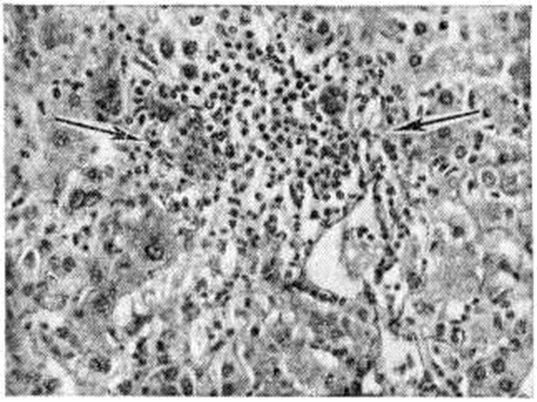

У больных вирус содержится в фекалиях, крови и моче. Хэвенс и Пол (W. Havens, J. Paul), Кругман (S. Krugman) и соавторами сообщили, что вирус в фекалиях больных чаще всего обнаруживается в инкубационный период. Вирус выделяется не только из содержимого кишечника, но и из крови, хотя и с меньшей регулярностью. Серьёзное эпидемиологическом значение имеют и вирусоносители. Основным источником возбудителя инфекции служат дети, среди которых чаще всего наблюдается бессимптомное носительство (смотри Носительство возбудителей инфекции), Число нераспознанных форм гепатита А, протекающих без типичных клин, симптомов, а также вирусоносителей значительно превышает число клинически выраженных форм гепатита. Гепатит А относится к группе кишечных инфекционных болезней и передаётся от больного (носителя) здоровому через заражённые фекалиями воду, пищевые продукты и при непосредственном контакте. Не исключается также роль мух в механической передаче вируса. Международная группа экспертов ВОЗ считает, что обычно вспышки чаще всего начинаются из-за фекального загрязнения воды и пищи. Однако распространение обычно происходит контактным путём. Описано много водных эпидемий гепатита А. Наиболее крупная из них наблюдалась в Индии (Дели) в 1951 год, когда в результате аварийного проникновения канализационных вод в водопровод гепатитом А заболело более 30 000 человек. Некоторые исследователи считают, что гепатит А передаётся и воздушнокапельным путём, хотя экспериментально это и не подтверждено. По мнению Международной группы экспертов ВОЗ, воздушно-капельная инфекция, вероятно, встречается редко. Доказана возможность при гепатите А передачи инфекции парентеральным путём (прививки, инъекции с лечебный целями и так далее). Инкубационный период при этом обычной длительности. Характерным является возрастное распределение заболеваемости — в основном болеют дети. При возникновении эпидемий возрастные соотношения могут значительно меняться. Наблюдается выраженная сезонность — заболеваемость резко возрастает в осенне-зимний сезон. Лица, переболевшие гепатитом А, остаются восприимчивыми к гепатиту В и наоборот. Как и при гепатите А, источником возбудителя инфекции при гепатите В являются больной человек и вирусоноситель. Вирус в крови больных содержится в течение всего инкубационного периода и весь острый период болезни. Опасность передачи гепатита В велика в силу высокой патогенности вируса. Например, Марри (В. Murray) считает, что 1,0 × 10-6 миллилитров плазмы вирусоносителя уже достаточно для заражения восприимчивого взрослого человека. Эти данные получены в результате прямых заражений волонтеров иктерогенной плазмой. В аналогичных наблюдениях Стокса (J. Stokes) и соавторами установлена длительность вирусоносительства. Предельный экспериментально установленный срок его — 5½ лет. По этим же наблюдениям у женщины — вирусоносителя, наблюдавшейся 3 года, при биопсии печени не было зарегистрировано каких-либо клинико-лабораторных и морфологически отклонений от нормы. Рождённый ею (с помощью кесарева сечения) и не кормленный материнским молоком ребёнок в двухмесячном возрасте заболел острым гепатитом В (подтверждённым заражением волонтеров) и через 2 года погиб от хронический формы болезни при явлениях фиброзного перерождения печени. Подобные наблюдения, повидимому, послужили основой для гипотезы о происхождении гепатита В, предложенной Ф. Бернетом, который считает, что вирус гепатита В является вариантом вируса гепатита А, передающимся внутриутробно; у плода при дальнейшем развитии и рождении либо манифестируется болезнь, либо формируется носительство, связанное с иммунологический толерантностью. Передача инфекции при гепатите В происходит парентеральным путём. Заражение может быть в результате пользования плохо стерилизованным инструментом (шприц, иглы, скарификаторы, скальпель и другие) при взятии крови, прививках, подкожном и внутривенном введении лекарств, при различных хирургических манипуляциях и так далее Чаще заражение происходит при переливании крови или плазмы. После введения в практику гамма-глобулина, а позднее коревой вакцины заболевания гепатитом В после противокоревой профилактики сывороткой крови доноров полностью прекратились. Международная группа экспертов ВОЗ (1973) высказала суждение, что одной только парентеральной передачей нельзя объяснить происхождение всех случаев заболевания гепатитом типа В. В литературе появились сообщения, что антиген гепатита В обнаружен в слюне, моче, желчи, кале больных и вирусоносителей. Как сообщает ВОЗ (серия технических докладов 512, 1973), в комарах, выловленных в некоторых районах Западный и Восточных Африки, методом встречного иммуноэлектрофореза обнаружен антиген гепатита В (соответственно в 28 и 18 группах комаров 12 видов). Однако участие кровососущих членистоногих в механизме передачи возбудителя инфекции при гепатите В может быть выяснено только после того, как будет доказана их способность передавать вирус при укусе. По данным Е. А. Пакториса (1972), не менее 50% всех заболеваний гепатит вирусный: взрослых относится к гепатиту В. Среди детей сывороточный гепатит встречается реже и главным образом в возрасте до 1 года. Заболевания гепатитом В не связаны с каким-либо сезоном и регистрируются в течение всего года. Повышению заболеваемости нередко предшествует массовая иммунизация, осуществляемая шприцами многократного пользования. Патологическая анатомияПатоморфология острого Гепатит вирусный изучена в основном на материале пункционных биопсий печени, так как летальные исходы редки (не превышают, как правило, 0,3%). Смерть чаще наступает от острого или подострого массивного некроза печени, патоморфология которого обстоятельно изучена (смотри Токсическая дистрофия печени). Метод биопсии позволил установить ряд изменений в слизистой оболочке кишечника. Морфологически изучение всех остальных систем и органов при не смертельных формах острого гепатита, тем более в инкубационном и в продромальном периодах, практически не осуществимо. При остром Гепатит вирусный морфологически изменения в продромальном периоде возникают за 1 — 7 дней до появления первых клин, признаков болезни и начинаются с активации и размножения звездчатых ретикулоэндотелиоцитов (купферовских клеток), а так-же эндотелия терминальных печёночных коллекторов, в зоне перехода синусоидного участка капилляров ацинуса в постсинусоидный — венозный. Вокруг терминальных печёночных коллекторов — периваскулярная инфильтрация из полиморфных мононуклеарных клеток (рисунок 4). В портальных трактах развивается отёк и обильная инфильтрация мононуклеарными клетками, напоминающими атипичные лимфоидные клетки или ретикулярные гистиоциты с небольшой примесью плазматических клеток. Возникает диффузная пролиферативная реакция купферовских клеток с образованием свободных клеточных форм. Часть купферовских клеток подвергается коагуляционному некрозу (смотри). В конце продромального периода присоединяются изменения гепатоцитов: анизонуклеоз с увеличением размеров ядрышек и преобладанием крупных ядер, многочисленные, главным образом патологический, митозы в различных зонах паренхимы, рассеянные белковые дистрофические изменения, преимущественно в гепатоцитах периферической зоны ацинусов (третья зона ацинуса). К началу клинического — желтушного периода болезни уже имеется выраженная патоморфологические картина. К ранее возникшим изменениям присоединяется вакуольная (баллонная) дистрофия и некрозы гепатоцитов с образованием эозинофильных телец, сходных с тельцами Каунсилмена (рисунок 5). В период максимальных изменений (2—5-я неделя болезни) вначале превалирует пролиферативная реакция мезенхимы. Воспалительные инфильтраты портальных трактов сливаются с инфильтратами паренхимы; в них нарастает количество плазматических клеток, появляются эозинофильные и единичные нейтрофильные лейкоциты. Нарастают баллонная дистрофия (рисунок 6) и некробиоз гепатоцитов, а также изменения стенок сосудов, что наряду с диффузной клеточной инфильтрацией нарушает структуру печёночной паренхимы. Отмечается значительная пролиферация желчных ходов с развитием полей «овальных» клеток и ложных желчных протоков. Выраженность изменений в различных ацинусах неодинакова. Изменения гепатоцитов в пределах одного и того же ацинуса различны вследствие асинхронности их возникновения и различных форм белковой дистрофии. В более тяжёлых случаях увеличивается количество и размер очагов некроза, главным образом в зонах периферии К ацинусов, вплоть до образования субмассивных и массивных некрозов. К концу периода максимальных изменений количество митозов гепатоцитов уменьшается, нарастает количество амитотически делящихся клеток, в желчных капиллярах — количество желчных тромбов; ретикулиновая строма паренхимы огрубевает, частично коллагенизируется, особенно в области терминальных печёночных коллекторов и по периферии осевых синусоидов. В очагах некроза возникают участки опустошения паренхимы (рисунок 7), более крупные в периферических отделах ацинусов; эти участки вначале содержат обломки гепатоцитов, позднее элиминируемых кровью либо частично фагоцитируемых на месте. В мелких очагах некроза появляются скопления лимфоцитов и крупных макрофагов — некрофагов, содержащих обломки клеток и буро-жёлтый пигмент — так называемый поздние узелки. Ретикулиновая строма в очагах некроза, особенно в третьих зонах ацинусов, спадается. В период обратного развития и реконвалесценции (6-я неделя болезни) постепенно уменьшается и исчезает клеточная инфильтрация, дистрофические изменения и полиморфизм гепатоцитов, более чётко выявляются участки опустошения паренхимы. К концу периода сохраняются лишь небольшие лимфоцитарно-фиброцитарные инфильтраты, ограничивающиеся портальными трактами, и «поздние» узелки (рисунок 8), значительно уменьшившиеся в размерах и количестве. Патологический процесс обычно полностью завершается на 7—8-й недель болезни. Долгое время могут сохраняться незначительные инфильтраты в портальных трактах — центральной вены дольки печени (рисунок 9) и остатки «поздних» узелков, очаговые скопления нагруженных буро-жёлтым. пигментом макрофагов, главным образом в третьих зонах ацинусов, незначительный полиморфизм гепатоцитов с некоторым избытком двуядерных клеток. Каждый из перечисленных морфологически признаков в отдельности не специфичен для острого Гепатит вирусный и встречается при многих других поражениях печени. Однако весь комплекс изменений и их типичная динамика характерны для Гепатит вирусный Близкая к этим картина изменений наблюдается при так называемый гепатитоподобных формах токсико-аллергических лекарственных гепатитов, дифференциальный морфологически диагноз которых нередко затруднителен. Электронно-микроскопическое и гистохимические исследования не выявляют специфических для Гепатит вирусный изменений. Гистохимические исследование показало, что в большинстве клеток усиливается синтетическая активность ядра и ядрышка в виде усиления реакции на РНК и белки. В цитоплазме гепатоцитов изменяются соотношения между содержанием отдельных функционально активных групп белковых молекул, что отражает нарушения синтеза и метаболизма белков; снижается активность ряда ферментов. Изменение активности ферментов в ткани печени не является специфичным для Гепатит вирусный и свидетельствует лишь о характере и степени дистрофических изменений гепатоцитов. В клетках, подвергающихся «просветлению» и баллонной дистрофии, гранулярный эндоплазматический ретикулум постепенно фрагментируется, разрушается; снижается содержание белков в цитоплазме, исчезает гликоген, развивается набухание и дезинтеграция митохондрий. В клетках, подвергающихся коагуляционному некрозу, происходит конденсация структур и усиление гистохимические реакций на белки, обусловленных дегидратационными процессами в цитоплазме и ядре. При образовании эозинофильных телец коагуляционный некроз захватывает нередко всю клетку, при парциальных некрозах — различные по величине и набору органелл фрагменты цитоплазмы, в дальнейшем образующие с участием лизосом аутофагические и секвестрирующиеся вакуоли. При электронно-микроскопическом исследовании в ядрах и цитоплазме гепатоцитов и купферовских клеток при гепатите. В обнаружены вирусоподобные частицы. Иммунофлюоресцентными и иммуноэлектронно-микроскопическими методами при этом определяется антиген, а в купферовских клетках также и иммунные комплексы. Особенности морфологически изменений печени позволяет выделять следующие основные формы Гепатит вирусный. При безжелтушной форме морфологически изменения печени характеризуются выраженной пролиферативной реакцией купферовских клеток и соединительной ткани портальных трактов при незначительных либо почти отсутствующих изменениях паренхимы. Затяжной острый гепатит морфологически отличается значительной растянутостью (иногда до нескольких месяцев) динамики изменений, особенно периодов максимальных изменений и реконвалесценции. Персистирующий острый гепатит отличается длительностью активной фазы (иногда до 1 года) без всякой тенденции как к обычному циклическому течению, так и к переходу в хронический гепатит. Характерно, что на протяжении всей болезни можно одновременно наблюдать все этапы обычного цикла изменений. При рецидивирующем остром гепатите на фоне всех морфологически изменений, типичных для циклической формы Гепатит вирусный, вновь появляются изменения, характерные для начальной его фазы. Морфологически различие холестатического и холангиолитического гепатита в ряде случаев затруднительно, поскольку и холестаз, и поражения желчных ходов составляют непременный компонент обычной циклической формы болезни. Холестатическими формами, очевидно, следует считать те, при которых внутрипечёночный холестаз выражен особенно ярко, достигая иногда степени значительного внепеченочного холестаза. В исходе Гепатит вирусный может наступить полная анатомическая реституция ткани печени. При более тяжёлом развитии процесса и в случае затяжного течения может развиться фиброз и цирроз печени (смотри), который обычно имеет характер постнекротического. ПатогенезПатогенез недостаточно изучен. Однако при сравнительном анализе клин, проявлений различных форм течения болезни у человека, биохимический исследований, патоморфологические и иммуноморфологические данных, главным образом биопсийного материала, с учётом результатов наблюдений по течению Гепатит вирусный у различных животных, можно принять общую схему патогенеза, изложенную в работах Г. П. Руднева (1966), В. М. Жданова и соавторами (1968), И. Ф. Баринского (1968), Б. К. Безпрозванного (1969), А. Ф. Блюгера (1969) и другие По этой схеме в первой фазе заражения возбудитель проникает в организм различными путями: при гепатите типа А — преимущественно энтеральным путём, при гепатите В — парентерально. В инкубационном периоде от момента заражения до развития клинической, проявлений болезни патологический процесс проходит ряд последовательных взаимосвязанных этапов: сначала ведущая роль принадлежит реакциям непосредственного взаимодействия между вирусом и макроорганизмом, затем при наличии условий для размножения возбудитель репродуцируется в тканях регионарных лимфатических, узлов; после его накопления следует первичная вирусемия (смотри). Однако достаточная информация о месте первичной репродукции вируса в организме отсутствует. Лишь основываясь на косвенных морфологически признаках, можно полагать, что при гепатите А она начинается в кишечнике, в его регионарных лимфатических, узлах. Затем следует генерализованное поражение ретикулоэндотелиальной системы и вторичная репродукция вируса в ней, что усугубляет повреждение клеток этой системы с образованием комплекса «вирус — клетка», не свойственного здоровому организму. В дальнейшем поражение вирусом печёночных клеток с их перестройкой на синтез вирусных белков ведёт к возникновению аутоиммунной реакции против печёночных клеток, играющей важную роль в прогрессировании процесса. Патологический процесс развивается как реакция гиперчувствительности замедленного типа с преобладанием клеточных аутоиммунных реакций (наряду со специфическими противовирусными реакциями). Нарастающее поступление вируса из регионарных лимфатических, узлов в общий ток крови, превышающее так называемый пороговую величину, обусловливает поддержание и дальнейшее развитие инфекционного процесса. В периоде клин, проявлений болезни, начиная с преджелтушного периода, в результате генерализации возбудителя происходит избирательное поражение ряда органов и систем организма. Определяющим клин, картину в дальнейшем является поражение печени. Иммунофлюоресцентными и электронномикроскопическими исследованиями было подтверждено наличие вирусного агента в ткани печени. Работы 70-х гг. 20 в. также свидетельствуют о том, что в клетках печени обнаруживается австралийский антиген. Так, Фурута (S. Fnruta) и соавторами (1975) методом прямой иммунофлюоресценции биопсийного материала печени выявил 2 типа локализации австралийского антигена: внутри цитоплазмы и на поверхности гепатоцита. У носителей этого агента, не имеющих признаков гепатита и с незначительными гистологический изменениями, австралийский антиген (смотри) обнаруживался на клеточной мембране. У лиц, больных циррозом печени, хронический гепатитом и первичной гепатомой, австралийский антиген локализовался в цитоплазме клеток. Степень поражения клеток печени зависит не только от течения болезни, степени репродукции вируса в организме, но и в значительной мере от индивидуальных особенностей больного, от состояния напряжённости неспецифического и специфического иммунитета, а тяжесть клин, течения болезни — от степени нарушения белков печёночных клеток и их синтеза. Вероятно, этот процесс связан не столько с непосредственным действием вируса, сколько является следствием вирусного поражения клеток. Таким образом, собственно острым инфекционным процессом можно считать лишь первые этапы его развития до генерализованного поражения ретикулоэндотелиальной системы. Клинической, период болезни, то есть гепатит в прямом смысле слова, является не началом болезни, а главным образом следствием первичного инфекционного процесса. Инфекционный процесс может оборваться на любом этапе. Если он оканчивается на ранних фазах, то болезнь протекает субклинически, стёрто или абортивно. И наоборот, процесс может задерживаться на определённых этапах, что влечёт за собой развитие затяжных и хронический форм, либо протекать с возобновлением волн генерализации и рецидивами болезни. При этом закономерно развиваются реакции повышенной чувствительности клеточного и гуморального типа, частота которых в 5— 10 раз превышает частоту внешних клин, проявлений аллергии и парааллергии при этой болезни. ИммунитетПроблема иммунитета, как и патогенеза, особенно при гепатите В, остаётся неразрешённой. Считают, что при гепатите В существует постинфекционный иммунитет слабой напряжённости. Вероятно, это объясняется дефектностью антигена или его слабой адаптацией к биол. средам организма. Если австралийский антиген довольно часто обнаруживают у больных гепатитом В в сыворотке крови, то антитела к нему встречаются весьма редко. По-видимому, при этом гепатите специфический иммунитет носит клеточный характер (Е. М. Тареев и соавторами, 1975). Предполагают, что при гепатите А новорождённые получают антитела от переболевших матерей, в силу чего иммунитет сохраняется у них до 1 года. Взрослые, перенеся гепатит А в детском возрасте, приобретают постинфекционный иммунитет специфического характера, сохраняющийся длительно, даже пожизненно. таким образом, иммунитет при Гепатит вирусный носит строго типовой характер, то есть иммунитет против гепатита А не предохраняет от заболевания гепатитом В и наоборот. Помимо специфического иммунитета, существенную роль в течении и исходах при Гепатит вирусный имеют и неспецифические факторы (интерферон, лизоцим, комплемент и другие). Клиническая картинаОстрый гепатитОстрый гепатит протекает циклически. В его течении различают четыре периода: 1) инкубационный; 2) продромальный, или преджелтушный; 3) желтушный, или период разгара болезни; 4) реконвалесценции. Принципиальных отличий в клин, течении гепатита А и гепатита В нет, однако последнему свойственна большая тяжесть течения и исходов. Продолжительность инкубационного периода при гепатите А составляет от 3 до 6 недель, при гепатите В — от 9 до 26 недель и более. Продромальный период длится 1—2 недель, отсутствует лишь в 0,8 — 5% случаев. Чаще проявляется диспептическим синдромом и лихорадкой, реже болями в правой половине живота. Могут наблюдаться катаральные явления, артралгический или ревматоидный синдром, различные аллергические реакции, геморрагии. Как правило, выражены астено-вегетативные явления. В крови — незначительная лейкопения, палочкоядерный сдвиг, умеренная эозинофилия, относительный лимфоцитоз. Закономерна гиперферментемия (ферментурия) — повышение активности аланинаминотрансферазы, а также ряда органоспецифических ферментов. К концу продромального периода отмечается гипербилирубинемия за счёт прямой фракции, уробилинурия, изменяются осадочные пробы. Продолжительность желтушного периода обычно не превышает 1 месяцев. Характеризуется быстро нарастающей желтухой (смотри) печёночноклеточного происхождения, выделением темно-коричневой мочи, содержащей желчные пигменты, обесцвечиванием испражнений, кожным зудом, увеличением и болезненностью печени, а нередко и селезёнки, лимфаденопатией, брадикардией и артериальной гипотензией, явлениями «острой инфекционной почки». Нарушаются экскреторная и внутрисекреторная функции поджелудочной железы. Отмечаются секреторные и двигательные расстройства желудочно-кишечного тракта, нарушения нервной системы в виде апатии, угнетённого состояния, плохого настроения, лёгкой раздражительности, эйфории, при тяжёлых формах — в виде сонливости или психомоторного возбуждения, эндокринопатий. В крови — эритро- и макроцитоз, лейкопения с относительной и абсолютной нейтропенией, эозинофилией, моноцитоз и лимфоцитоз, ретикуло-плазмоцитарная реакция костного мозга, умеренная тромбоцитопения; РОЭ обычно замедлена. Центральное место занимают биохимический сдвиги, обусловленные функциональными нарушениями печени: нарушение пигментного обмена — гипербилирубинемия (смотри), главным образом за счет повышения прямой фракции с увеличением (соответственно тяжести болезни) билирубинового показателя; билирубинурия, снижение концентрации стеркобилина в кале. Выражены нарушения синтетической и комплексообразующей функции печени — гипопротеинемия, умеренное снижение относительного содержания альбуминов, преходящее увеличение фракций α2-и отчасти γ-глобулинов с изменением альбумино-γ-глобулинового и альбумино-глобулинового коэффициентов, резкое снижение α-липопротеидов с увеличением коэффициента β-липопротеиды/α-липопротеиды. Наблюдаются положительная реакция на парапротеины и изменения осадочных проб, снижение содержания протромбина, фибриногена, изменения во всех фазах свёртывания крови; нарушения ферментного равновесия — повышение активности таких печёночноклеточных изоферментов, как альдолаза, аминотрансферазы в печени, крови, моче и других органах и тканях, а также изменение активности органоспецифических ферментов и их изоферментов с нарушением субклеточной локализации. Повреждаются связи апоферментов с коферментами; отмечаются изменения межуточного обмена — количественные и качественные сдвиги аминокислотного состава сыворотки крови и ткани печени, нарушение мочевинообразовательной функции печени; нарушается углеводный обмен — спонтанная фруктозурия, изменения анаэробного гликолиза и гликонеогенеза; изменяется липидный обмен — снижение содержания холестерина, в основном за счёт его эфиров, с уменьшением показателя эстерификации, повышение содержания желчных кислот; изменяется содержание микроэлементов. Периоду реконвалесценции свойственно обратное развитие симптомов — восстановление аппетита, ослабление желтухи, полиурия, сокращение размеров печени, обратное развитие функциональных сдвигов. Продолжительность периода обычно 7—15 дней, но может достигать 2—3 и более месяцев. По течению заболевания и выраженности ведущих симптомов — степени интоксикации, интенсивности желтухи и гепатомегалии — в остром Гепатит вирусный можно выделить лёгкие, среднетяжёлые и тяжёлые формы с включением в последнюю группу больных с массивными и субмассивными некрозами печени, то есть острой и подострой атрофией печени, или Гепатит вирусный злокачественного течения. Гепатит вирусный с желтухой протекают примерно одинаково часто в лёгкой и среднетяжёлой формах, составляющих 85—95% всех случаев, и только 5—10% приходится на долю тяжёлых форм. Лёгкое течение характеризуется слабо выраженной интоксикацией, лёгкой желтухой (содержание билирубина в крови не более 5 миллиграмм%, по Ендрашику), небольшим увеличением печени, реже селезёнки, умеренными сдвигами осадочных проб (сулемовой до 1,5 миллилитров, тимоловой до 8 единиц при норме 1—4 единиц). Активность альдолазы не превышает 20—25 единиц, аминотрансфераз — 300—400 единиц, активность холинэстеразы, аргиназы, урокиназы и других ферментов остаётся в пределах нормы. Содержание общего белка крови меняется мало, ко 2— 3-й недель болезни отмечается умеренный сдвиг в сторону гипергаммаглобулинемии, концентрация холестерина в пределах нормы или слегка снижена, коэффициент β-липопротеиды/α-липопротеиды умеренно повышен. Лапароскопически обнаруживают увеличенную коричневато-красного цвета с «зеркальной» поверхностью печень, что объясняется её гиперемией, отёком и лимфостазом. Состояние больного быстро улучшается, нормализуются размеры и функции печени, общая длительность желтухи не превышает 2—3 недель; средняя длительность пребывания больного на койке — 22 дня. Среднетяжёлой форме свойственна интоксикация, которая проявляется отсутствием аппетита, тошнотой (иногда рвотой), головной болью, значительно более выраженной желтухой (билирубинемия 5—10 мг%) и гепатомегалией, спленомегалией; сопровождается кожным зудом, язык обложен, сухой; живот вздут, появляется запор, реже поносы; отмечаются боли в животе. Могут быть носовые кровотечения. Как правило, наблюдаются брадикардия и гипотензия. Изменения функциональных проб печени выражены более значительно: сулемовая проба 1,5—1,3 миллилитров, тимоловая 8—10 единиц, активность альдолазы 30—35 единиц, аминотрансфераз 400—500 единиц. Резко изменяются активность органоспецифических ферментов, показатели азотистого обмена. Значительно снижено количество альбуминов, повышено содержание α<./sub>2-глобулинов, изменено содержание β- и γ-глобулинов, обнаруживаются парапротеины. При лапароскопии — «большая красная печень» с выраженным отёком и лимфостазом капсулы, нежными висцеропариетальными спайками, округлым краем; желчный пузырь бледный, отёчный, спавшийся; на поверхности печени местами мелкоточечные кровоизлияния и щели западений в участках некрозов. Перелом в течении болезни начинается с диуретического криза, появляется аппетит, улучшается сон. Продолжительность всех сдвигов значительно большая, чем при лёгкой форме, например, длительность желтухи около 30 дней. Средняя продолжительность пребывания больного в стационаре 28 дней; общая длительность болезни 6—8 недель. Основной признак и критерий тяжести при тяжёлой форме — поражение центральной нервной системы: в одних случаях больные эйфоричны, не осознают тяжести своего состояния и не предъявляют жалоб, в других — сонливы, вялы, ритм сна нарушен, отмечаются головокружения, головные боли. Преджелтушный период обычно бывает бурным, с высокой лихорадкой, анорексией, тошнотой, рвотой, которые усиливаются в желтушный период болезни. Симптоматика желтушного периода резко выражена: желтуха шафранного оттенка (уровень билирубина достигает 15—20—40 миллиграмм%), кровоточащий гингивит и другие геморрагические проявления (носовые, маточные кровотечения и прочее); язык густо обложен, сухой; печень имеет малые размеры или быстро уменьшается, консистенция её тестоватая. Селезёнка, как правило, не увеличена. Стойкая брадикардия, при прогрессировании болезни сменяющаяся тахикардией. Отмечается значительная гиперферментемия — активность аминотрансферазы более 600 единиц, альдолазы — более 35 единиц, выраженное снижение содержания альбуминов, высокое содержание α2- и β-глобулинов, γ-липопротеидов, парапротеинов, низкий уровень холестерина (90—50 миллиграмм%), протромбина; (40—50%), снижение показателей сулемовой пробы до 1,2—0,7 миллилитров Лапароскопически обнаруживают такую же картину, что и при Гепатит вирусный средней тяжести, но более пёструю из-за резкой гиперемии, больших участков некроза, отёка, большого числа кровоизлияний и значительного количества щелей западения. Прекращение рвоты, тошноты, появление аппетита, восстановление сна, исчезновение головных болей, нормализация пульса и АД, диуретический криз — первые предвестники стабилизации патологический процесса; вслед за этим начинается его обратное развитие. Выздоровление наступает обычно на 9—10-й недель болезни. Однако примерно в 4—10% случаев тяжёлые формы Гепатит вирусный могут закончиться острым массивным некрозом печени и развитием злокачественного варианта болезни. Неблагоприятными факторами, отягощающими течение болезни, считаются поздняя госпитализация или преждевременная выписка из стационара, тяжёлый физических труд, злоупотребление алкоголем в преджелтушной стадии болезни, серьёзные психические переживания, перенесённые незадолго до Гепатит вирусный, истощающие и аллергизирующие организм заболевания, алиментарная недостаточность, лекарственная непереносимость, присоединение вторичной инфекции, оперативные вмешательства, особенно произведённые по ошибочным показаниям, беременность на последних месяцах. Несомненную роль играет возрастной фактор: летальность от Гепатит вирусный с массивным или субмассивным некрозом печени значительно выше среди детей (особенно грудного возраста) и в пожилом возрасте. Среди признаков, дающих основания для возможно более раннего распознавания злокачественного течения Гепатит вирусный, можно указать на выраженные нервно-психические расстройства (подавленность или возбуждение, сонливость или бессонница, вялость, отвращение к пище, адинамия), сочетающиеся обычно с интенсивно нарастающей желтухой, значительной лихорадочной реакцией, болевым синдромом, тахикардией, наклонностью к кровотечениям, развитием асцита и отёков, выраженной болезненностью и прогрессирующим сокращением в размерах печени, значительными нарушениями со стороны других органов (миокарда, почек и другие). Из лабораторных показателей следует отметить лейкоцитоз, ускоренную РОЭ, низкое содержание тромбоцитов, глубокие сдвиги всех основных функций печени — дезаминирующей, антитоксической, обмена билирубина, углеводного, белкового обмена, электролитного баланса и другие. Одним из существенных симптомов является падение активности печёночноклеточных ферментов при повышении содержания билирубина в крови, то есть билирубино-ферментная диссоциация, а также резкое снижение протромбинового индекса. При злокачественной форме Гепатит вирусный возможно развитие прекоматозного и коматозного состояния (смотри Кома); в значительной части случаев развивается атрофия печени с летальным исходом (смотри Печень), однако возможно выздоровление отдельных больных с полной регенерацией печени либо клин, излечение с формированием «рубцовой» печени. Указывают также на более частое развитие при этих формах хронический гепатита и постнекротического цирроза печени, а также острого цирроза печени (смотри Циррозы печени). Безжелтушная форма Гепатит вирусный отличается от желтушной меньшей выраженностью клин, симптоматики и отсутствием синдрома гипербилирубинемии с одновременным энзимологический сдвигом и частичным нарушением пигментного обмена (потемнение мочи, особенно в конце продромального периода, кратковременное обесцвечивание испражнений), однако поражение печёночных клеток нередко оказывается значительным. Частота безжелтушных форм колеблется в широких пределах; на каждого больного с желтухой приходится такое же число безжелтушных форм. Субклиническая (латентная, или инаппарантная) форма — редуцированная форма болезни, при которой структурно-функциональные изменения не сопровождаются клин, проявлениями, но закономерно проявляются ферментативными и реже сдвигами других лабораторных данных. Обычно выявляется среди лиц, находившихся в контакте с заболевшими желтушной формой; определяется на основании лабораторных, и главным образом энзимологический тестов. Безжелтушные, субклинические, латентные формы Гепатит вирусный имеют огромное эпидемиологический значение и в то же время по частоте возможных неблагоприятных исходов существенно не отличаются от желтушных форм Гепатит вирусный Острый Гепатит вирусный затяжного течения не укладывается в обычные для циклической формы (1—2 месяцев) сроки, а продолжается 3—8 месяцев и более. Среди причин, способствующих затяжному течению, имеют значение поздняя госпитализация, психические и физ. травмы, сопутствующие заболевания (хронический заболевания желудочно-кишечного тракта и желчных путей, сахарный диабет, туберкулез, алкоголизм и другие), пожилой возраст больных. При холестатическом (холангиолитическом) Гепатит вирусный на первый план в клин, картине болезни выступает симптоматика механической желтухи (внутрипечёночная обтурация), что создаёт значительные трудности в отграничении подобной формы от внепеченочной желтухи. Наблюдается чаще у женщин. Клинической, симптоматика подробно описана Уотсоном и Хоффбауэром (С. Watson, F. Hoffbauer, 1946). Для преджелтушной стадии характерна клин, триада — лихорадка, артралгии, уртикарная сыпь. Определяющим признаком является интенсивная и продолжительная (2—4 месяцев) желтуха со слабоокрашенным или полностью обесцвеченным стулом, отрицательной реакцией в моче на уробилиноген, упорным кожным зудом с первых дней заболевания при удовлетворительном самочувствии больного, с незначительным увеличением печени, нередким появлением на высоте болезни симптома Курвуазье (в связи с регионарным лимфаденитом, серозным воспалением и отёком стенки желчного пузыря), ускорением РОЭ, повышением содержания в крови щелочной фосфатазы, холестерина, фосфолипидов, своеобразном зеленоватом колорите поверхности печени по данным лапароскопического исследования. Отличается благоприятным прогнозом, в редких случаях возможно развитие билиарного цирроза печени. Персистирующему гепатиту присуще длительное сохранение активности инфекционного процесса без тенденции к обратному развитию на протяжении нескольких месяцев. При морфологически и лапароскопическом исследовании у больных отмечается картина «большой красной» или «большой белой» печени, свойственная острой фазе Гепатит вирусный Подробно описан Сметаной (Н. Smetana, 1957). Встречается редко. В клинической картине доминируют «брюшной дискомфорт», диспептические явления, болевой синдром. Печень увеличена и уплотнена, функциональные пробы на протяжении болезни значительно изменены. Всегда заканчивается полным выздоровлением. Обострения и рецидивы Гепатит вирусный, близкие по своему генезу, наблюдаются в первые 2—4 месяцев примерно в половине случаев после прекращения стационарного лечения. Они могут быть связаны с физ. или нервным перенапряжением, ранним прекращением постельного режима и лечения, нарушением диеты или интеркуррентной инфекцией, а также с применением в период санаторно-курортного лечения противопоказанных грязевых процедур и ванн. Отмена гормонов при лечении больных кортикостероидами может быть причиной рецидивирующего течения (так называемый стероидные рецидивы Гепатит вирусный). Предвестниками рецидивов являются ухудшение общего самочувствия, повышение температуры и возникновение болевого синдрома, нарастание активности сывороточных ферментов (особенно холинэстеразы и аргиназы). Клинически рецидивы проявляются теми же симптомами, что и предшествующий острый период болезни, однако их течение оказывается более лёгким и менее продолжительным. В ряде случаев наблюдаются лишь изолированные волны гиперферментемии — так называемый биохимические рецидивы. Остаточные явления могут сохраняться на протяжении нескольких недель и даже месяцев в виде жалоб больных астено-вегетативного характера, болевых и диспептических явлений. В этих случаях возможны субиктеричность склер, слизистой оболочки неба и (реже) кожных покровов с соответствующими нарушениями пигментной функции печени (увеличение непрямой или, реже, прямой фракции билирубина в крови, патологический уробилинурия), умеренное увеличение печени, изменение её функциональных проб (гиперпротеинемия, гипергаммаглобулинемия, положительные сулемовая и тимоловая пробы, реакция Вельтманна). Отмечаются нарушения экскреторной функции печени и микроциркуляции и, наконец, морфологические признаки перенесённого острого процесса — следы очагов запустения паренхимы с наличием тонких соединительнотканных волокон и очаговой коллагенизацией стенок синусоидов, скопления желчного пигмента, липофусцина или железосодержащего пигмента в макрофагах, незначительные (главным образом фиброцитарные) инфильтраты в портальных трактах и перипортальных областях, остаточные дистрофические изменения печёночных клеток в виде светлого набухания, отложения жира с одновременным уменьшением запасов гликогена. Как правило, «морфологическое исцеление» занимает 12—16 недель, а в ряде случаев наступает в гораздо более поздние сроки. Болевой синдром, возникающий через различные сроки после перенесённого Гепатит вирусный, характеризуется постоянными или приступообразными болями в правом подреберье с иррадиацией в спину (нередко при сочетанном поражении поджелудочной железы), усиливающимися после приёма пищи либо физических напряжения, переутомления, переживаний. Этот синдром обычно не сопровождается развитием желтухи, диспептических явлений, повышением температуры, изменениями функциональных проб печени, гепатомегалией. Такое состояние более чем в 2/3 случаев обусловлено дискинезией желчных путей. У таких больных, как правило, отмечаются изменения со стороны нервной системы — раздражительность, повышенная возбудимость, нарушение сна, головная боль. Дискинетические расстройства бывают обычно достаточно стойкими. Возможно также возникновение холецистита и холангита, обусловленных вторичной бактериальной флорой или самой вирусной инфекцией и характеризующихся субфебрилитетом, наличием воспалительных элементов в осадке желчи, изменениями периферической крови. Лапароскопически — картина перигепатита и перихолецистита. Примерно у 1/3 реконвалесцентов наблюдается сочетание диспептических явлений с исхуданием, болями в эпигастрии, иррадиирующими влево. Возможны нарушения внешней внутрисекреторной функции поджелудочной железы, снижение содержания липазы и амилазы в дуоденальном содержимом. Нередко имеются нарушения желудочной секреции с угнетением её за счёт расстройства нервнорефлекторной регуляции сокоотделения. Астено-диспептический синдром характеризуется сочетанием болевых, диспептических и астено-вегетативных явлений без лабораторных и морфологически признаков поражения печени. Термин предложен Уолшем и Шерлок (V. Walshe, S. Sherlock, 1946) после подробного описания синдрома Бенджамином и Хойтом (J. Benjamin, R. Hoyt, 1945). Преобладают жалобы астенического характера: повышенная утомляемость, подавленное настроение, бессонница, слабость, раздражительность, чувство тревоги, тремор. Могут наблюдаться ипохондрическое или депрессивное состояние, нарушения либидо, импотенция. У больных отсутствует аппетит, они худеют; отмечаются непереносимость жирной пищи, тошнота, чувство полноты или давления в области желудка или правого подреберья, усиливающиеся при длительном пребывании в положении сидя, при ходьбе, стоянии, езде в автомобиле. Единственным объективным признаком этого синдрома является некоторое уплотнение и увеличение печени. В происхождении синдрома большое значение придаётся психоневротическим сдвигам. Подчёркивается большая частота его развития у лиц умственного труда. Симптоматика может длиться от нескольких месяцев до нескольких лет, чаще не более года. Постгепатитной гипербилирубинемии свойственно периодическое повышение в крови билирубина, в ряде случаев с видимой лёгкой желтухой на протяжении нескольких дней, реже недель при нормальном анатомическом и функциональном состоянии печени. Встречается чаще у мужчин. Содержание билирубина в сыворотке крови в большинстве случаев превышает 1 миллиграмм% (в среднем 2—3 миллиграмм%), в основном за счёт непрямой фракции. Билирубинурия отсутствует. Появлению желтухи, как правило, предшествуют физических или психическая нагрузка, интеркуррентные инфекции, нарушение диеты. В период повышения билирубина может отмечаться преходящая гепатомегалия, иногда спленомегалия. Лабораторными и инструментальными методами выявляется нарушение поглотительноэкскреторной функции печени. Могут наблюдаться признаки повышенного гемолиза эритроцитов, высокое содержание гемоглобина. Морфологически на фоне почти обычной архитектоники печени отмечается скопление мелкого, пылевидного золотисто-бурого пигмента, при электронно-микроскопическом исследовании представляющего элементы желчи и, реже, гранулы липофусцина, с преимущественной локализацией вблизи билиарных полюсов гепатоцитов, нарастание числа «гликогеновых» ядер и гиперплазия агранулярных профилей эндоплазматического ретикулума, изменения синусоидального полюса гепатоцитов, различные стадии и формы ожирения печёночных клеток. В основе постгепатитной гипербилирубинемии лежит прежде всего повреждение функций захвата и конъюгации билирубина в связи с недостатком трансферазы глюкуроновой кислоты, а также нарушение других звеньев обмена билирубина, и в первую очередь экскреции желчного пигмента. В патогенезе незначительной части постгепатитных гипербилирубинемий основное значение имеет повышение гемолиза и катаболическая форма образования шунтового билирубина, что даёт основания причислять их к гемолитическим желтухам, от которых они отличаются нормальной продолжительностью жизни циркулирующих эритроцитов. Длительность болезни обычно более 6 месяцев, течение благоприятное, без наклонности к прогрессированию. Постгепатитная гепатомегалия — изолированное увеличение печени, обнаруживаемое у реконвалесцентов спустя 1—2 года; клинической, проявления, нарушения функции и архитектоники печени отсутствуют. Это состояние чаще всего обусловлено остаточным фиброзом портальных полей и, частично, перипортальных участков ткани органа, нередко с сетью тонких коллагеновых волокон, врастающих в паренхиму из фиброзированных портальных трактов, а также сетчатым фиброзом (перицентральным, перивенозным) долек и очаговым (сетчатым и несетчатым) фиброзом паренхимы. Реже, в случаях излечения острой и подострой атрофии, гепатомегалия обусловлена грубоузловым фиброзом; иногда в основе её лежит гиперплазия и гипертрофия клеток печени. Хронический гепатитХронический гепатит развивается в 5—10% случаев после перенесённого острого процесса, чаще после тяжёлых, затяжных форм болезни (особенно гепатита В), при наличии сопутствующих заболеваний желудочно-кишечного тракта и желчных путей, предшествующего алкоголизма, интоксикаций. Хронический Гепатит вирусный возможен у лиц пожилого возраста, поздно госпитализированных в стационар, а также недостаточно интенсивно леченных в остром периоде или рано приступивших к физ. работе. Формирование хронический Гепатит вирусный наблюдается либо вслед за желтушным периодом или периодом реконвалесценции, либо после клинически латентного периода, в некоторых случаях — без предшествующей острой стадии (так называемый первично хронический Гепатит вирусный). Симптоматика хронический гепатита в общем повторяет симптоматику острого, особенно в периоды обострений, которым могут предшествовать свойственные острому гепатиту продромальные явления. Больной жалуется на слабость, особенно по утрам, утомляемость, чувство тяжести и боли под ложечкой, диспептические явления — потерю аппетита, непереносимость жирной пищи, вздутие живота, тошноту, понос. При выраженных обострениях отмечаются желтуха, зуд, похудание, периодическая лихорадка. Печень постоянно увеличена, с гладкой поверхностью, болезненная; увеличение селезёнки определяется реже, изредка — феномен «сосудистых звёздочек» и «печёночных ладоней». Об активности процесса свидетельствует гиперферментемия, диспротеинемия с гипергаммаглобулинемией, сдвиги осадочных проб, повышение содержания иммунных глобулинов. При лапароскопии обнаруживается «большая белая» или «большая пёстрая» печень, нередко с узлами регенератов, с поражением обеих долей или только одной. Существуют две формы хронический Гепатит вирусный: персистирующий, или доброкачественный, с возможным выздоровлением и хронический активный, или прогрессирующий, с исходом в цирроз с ремиссиями и обострениями. Вирусный цирроз печени является редким исходом Гепатит вирусный (0,8—1% случаев), но занимает значительный удельный вес (3/4 всех случаев) среди циррозов различной этиологии. Часто он развивается спустя годы после выздоровления; является одной из основных причин развития печёночной комы с летальным исходом. Возникает после всех форм Гепатит вирусный, чаще после тяжёлых, затяжных и рецидивирующих. Наблюдается преимущественно у мужчин. Среди факторов, способствующих развитию цирроза, основное место занимают тяжесть и стойкость самой вирусной (начальной) инфекции и возможные реинфекции. Может быть с различными морфологически изменениями, однако среди них преобладают постнекротические. Клин, характеристика складывается из печёночноклеточной недостаточности, портальной гипертензии, желтухи, поражения ретикулоэндотелиальной системы, гемодинамических нарушений, лихорадки, изменений со стороны нервной и эндокринной систем. Исходя из особенностей развития, выделяют ранний и поздний цирроз, а также цирроз после длительно протекавшего Гепатит вирусный ДиагнозРаспознавание типичных случаев Гепатит вирусный, особенно во время эпидемиологическом вспышек, особых трудностей не представляет. Основная задача — раннее и наиболее полное выявление больных Гепатит вирусный ещё в продромальном периоде болезни, а также больных безжелтушными и субклиническими формами. Диагностика основывается на неспецифическом симитомокомплексе (диспептический, артралгический, катаральный и астенический синдромы), признаках интоксикации (повышение температуры, снижение аппетита вплоть до полной анорексии и отвращения к еде), раннем появлении гепато- и спленомегалии, наличии билирубина и белка в моче, учёте эпидемиологический данных; существенным дополнительным методом являются ферментологические исследования. Большие перспективы открываются в связи с вирусологический и серологические методами, в том числе с методами, направленными на выявление антигена гепатита А и гепатита В. В разгар болезни диагноз подтверждается данными лабораторных анализов: повышение содержания прямого билирубина, выраженные глобулиновые сдвиги, изменение осадочных проб, гиперферментемия, некоторые сдвиги в картине периферической крови (лейкопения, замедленная РОЭ, лимфомоноцитарная реакция). Диагноз гепатита В основывается на некоторых клинический особенностях (постепенное начало, отсутствие лихорадки, частота артралгических явлений, тяжёлое течение болезни с большей частотой неблагоприятных исходов), установлении факта гемотрансфузий, производившихся в сроки, укладывающиеся в свойственный этому заболеванию инкубационный период, и, наконец, на выявлении в крови больного гепатитом В австралийского антигена. Распознавание хронический Гепатит вирусный и вирусного цирроза печени при отчётливой клинической, картине не сложно. В диагностике латентно протекающих форм и при отграничении хронический гепатита от цирроза существенное значение имеют инструментальные методы — пункционная биопсия, лапароскопия, радиоизотопное исследование, ангиография, реовазография. В диагностике гепатом с успехом используется определение иммунопреципитационными методами α-фетопротеина в крови больных. В продромальном периоде Гепатит вирусный следует проводить дифференциальный диагноз с острым гастроэнтероколитом, пищевыми токсикоинфекциями, гриппом, адено- и энтеровирусной инфекцией, ревматизмом, инфекционным мононуклеозом; при атипичном его течении — с различными патологический процессами, включая острый холецистит, панкреатит, аппендицит, психические заболевания и тому подобное Ведущее значение в диагностике имеет констатация развития интоксикации, анорексии, гепатомегалии, гиперферментемии и антигенемии, свойственных Гепатит вирусный, а также клинической, симптомов и лабораторных данных (копрологические, серологические, микробиологические и гематологические). Желтушная форма Гепатит вирусный требует отграничения от других видов желтух — гемолитической, механической, медикаментозной, различных гипербилирубинемий. Для гемолитической желтухи свойственны низкий билирубиновый показатель, сохранность функции печени, лабораторно — признаки повышенного гемолиза. Дифференциальная диагностика с внепеченочным холестазом сложна, особенно в случае холестатического гепатита, при этом клинико-лабораторные показатели и даже морфологически признаки не могут быть достаточно надёжным критерием. Решающее значение придаётся рентгеноконтрастным методам: чрескожной холангиографии (смотри), ретроградной холангиографии при дуоденофиброскопии и другие Разграничение Гепатит вирусный и лекарственных поражений печени основывается на меньшей продолжительности при последних преджелтушного периода и периода желтухи, большей выраженности аллергических проявлений в начальном периоде болезни, наличии лейкоцитоза, менее высокой гипербилирубинемии, относительной сохранности функции печени, высокой активности щелочной фосфатазы; более существенна для диагностики пункционная биопсия печени, выявляющая своеобразие морфологически и ультраструктурных изменений. Морфологически методу принадлежит решающее значение и в отграничении Гепатит вирусный от различных гипербилирубинемий. Дифференциальная диагностика Гепатит вирусный с гепатитами при других вирусных (жёлтая лихорадка, реовирусы, аденовирусы, простой герпес и другие) и инфекционных болезнях бактериальной природы проводится при анализе клинико-лабораторных и эпидемиологический данных в их совокупности. Острый алкогольный гепатит отграничивается от Гепатит вирусный на основании развития желтухи после злоупотребления алкоголем, наличия лихорадки, лейкоцитоза, болей в верхнем квадранте живота справа, своеобразия морфологически картины с обнаружением алкогольного гиалина. Лабораторная диагностикаЛабораторная диагностика, основанная на выделении и идентификации возбудителя Гепатит вирусный или определении специфических антител к нему, находится в стадии экспериментальной разработки. В комплекс лабораторных исследований при Гепатит вирусный (кроме обычных исследований крови, мочи, желчи, кала и другие) входят биохимический, морфологически (биопсия печени), иммунологический и вирусологический методы. В конце продромального периода в сыворотке крови больного отмечается нарастание количества общего билирубина, главным образом за счёт связанной фракции (смотри Билирубин). В желтушном периоде болезни отмечается гипербилирубинемия. Динамическое увеличение концентрации свободного (непрямого) билирубина и моноглюкуронид-билирубина, а также длительное сохранение его на высоком уровне может свидетельствовать о тяжёлом течении болезни либо о возможности наступления прекоматозного или коматозного состояния. Задержка в нормализации этих показателей в периоде реконвалесценции характеризует неполное восстановление функции печени. В начале желтушного периода болезни в моче определяется билирубин (отсутствующий в норме), уробилиноген (по тёмному цвету мочи). Сочетание желтухи с темным цветом мочи, не содержащей билирубина, указывает на гемолитический генез желтухи. Понижается количество стеркобилина в кале (обесцвеченные испражнения).